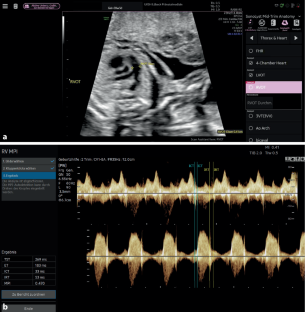

Abb. 2